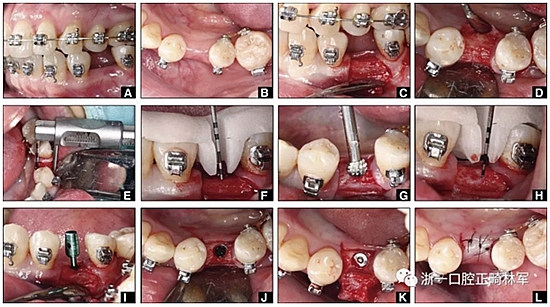

完全固定的Damon Q設(shè)備(加利福尼亞州Glendora的Ormco)與制造商指定的弓絲和附件一起使用。下頜弓,一開始放入0.014英寸的鎳鈦弓絲,5個月后放入0.014×0.025英寸的鎳鈦弓絲。舌側(cè)扣和鏈圈放置在下頜尖牙和第二前磨牙上以控制扭轉(zhuǎn)。在治療的第7個月,將下頜弓絲換成0.017× 0.025英寸的β鈦絲。另一個舌側(cè)扣和鏈圈放置在下頜左側(cè)第三磨牙上以提供近中牽引力(圖9)。在16個月的治療結(jié)束時,所有的扭轉(zhuǎn)都得到了矯正,缺牙間隙縮小到8 mm(圖8),但由于頰側(cè)骨板的嚴重吸收,牙槽嵴的寬度仍然很窄(約3 mm)(圖9)。通過正畸移動下頜左側(cè)第二前磨牙,在前磨牙之間產(chǎn)生一個種植部位。在第一和第二前磨牙之間的弓絲上放置一個推簧,并將舌側(cè)扣和鏈圈放置在第一前磨牙和第三磨牙之間(圖9),在頰側(cè)和舌側(cè)施加力。施力均為輕力,每個表面上約2盎司(28.3 cN)以控制牙根側(cè)面的吸收。

圖8

圖9

圖10.經(jīng)過7個月后,以每月1毫米的速度牽引下頜左側(cè)第二前磨牙,正畸產(chǎn)生的種植部位長約7毫米。通過使用固定矯治器保持間隙6個月。根尖X線片顯示第二前磨僅有少量牙根遠中面吸收。

圖12.將種植體植入正畸產(chǎn)生的間隙中的步驟:A,將下頜左側(cè)第二前磨牙向遠中移動以在前磨牙之間產(chǎn)生間隙; B,種植部位的咬合面觀; C,一個水平切口和兩個垂直切口,距相鄰牙齒1.5mm的距離; D,暴露的牙槽嵴的咬合面觀; E,測量牙槽嵴的寬度約6mm; F,手術(shù)導板顯示預(yù)備冠頸部的位置距離骨牙槽嵴頂僅1毫米; G,用球鉆修整牙槽嵴; H,建立3mm從手術(shù)導板的頸部輪廓到骨嵴的距離,以實現(xiàn)必要的生物學寬度; I,引導針顯示了截骨的角度; J,3.5×10mm種植體完全置于骨內(nèi); K,一個覆蓋螺帽就位; 和L,縫合。